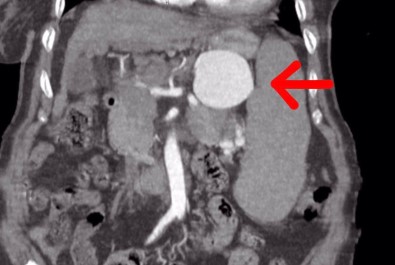

Degerlendirmeler sonrasi ilaç tetkikleri istediklerini belirten Dr. Taban, "Yapilan tomografide teyzemizde dalak arterinde oldukça genis dev diyebilecegimiz anerizmanin yani baloncuklasmanin oldugunu gördük. Normalde dalak anerizmasi diyebilmemiz için baloncuklasma diyebilmemiz için 20 milim yani 2 santimin üstüne çikmasi lazim. Ama gördügümüzde bizde sasirdik. Çünkü yaklasik 7 santimi geçen bir dalak anerizmasi vardi. Hastanin bu anerizmanin içerisinde tamamen kan doldugu için her an patlama riski vardi. Allah korusun hastanin hayatini kaybetme riski ile de karsi karsiyaydik. Hasta ile ilgili hemen multidisipliner olarak bir degerlendirme yaptik. Hem gastroenteroloji, hem genel cerrahiden Serhat hocamiz, hem radyoloji klinigimiz ile beraber degerlendirme yaptik. Hastamizin 15 yildir mücadele verdigi bir karaciger sirozu da bizim kararlarimizda etkili oldu” dedi.

75 yasindaki hastanin Sirnak’ta ameliyat edilmesinin riskli oldugunu ve bu durumu hem hastaya hem de hasta yakinlarina söylediklerini aktaran Dr. Taban, "Hastamiz ve yakinlari yillardir hastanemizde tedavi olmak istediler. Bizde hastamiza açik cerrahinin ilk etapta riskli olabilecegini düsündük. Çünkü karaciger sirozuna bagli ve diger hastaliklara bagli olarak kan degerlerinde inanilmaz derecede bir bozukluk vardi ve cerrahi oldukça riskliydi. Biz öncelikle anjiyo yoluyla kasiktan girerek dalak anerizmasina ulasip, dalak anerizmasinin içerisini kapatmayi ve dalak damarina bir stent koyarak oradaki anerizmanin patlamasini engellemeyi çalistik. Anjiyomuz yaklasik 1,5-2 saat sürdü. Anjiyo salonuna aldik hastamizi, anjiyo sirasinda ne kadar ugrassak ta dalak damari o kadar genislemiski kendi etrafindaki damarlar ile beraber döndügü için dalak damarini bir türlü kateterize edemedik. Dalak damarinin içerisine ulassak da ardina ulasamadik. Yaptigimiz tekrar degerlendirmesinde hastamizin ameliyat edilmesinin daha dogru olacagini düsündük. Hastamizi açik cerrahi vakasina aldik. Açik cerrahi vakasinda genel cerrahi ile birlikte, önce karindan ufak bir keski ile girdik. Girdigimizde karsilastigimiz manzara aslinda tomografide gördügümüz manzaradan veya anjiyoda gördügümüz manzaradan daha da kötü haldeydi. Dalak damari anerizmasini onararak hastamizi ameliyattan çikardik. Ameliyat sonrasinda da hastamizin bir yogun bakim ihtiyaci olmadi. Servise aldik. Bundan sonraki degerlerimize baktigimizda da ciddi bir kan ihtiyaci olmadi. Daha sonraki kontrol kanlarimizda gayet iyi oldugu gözüküyor" dedi.